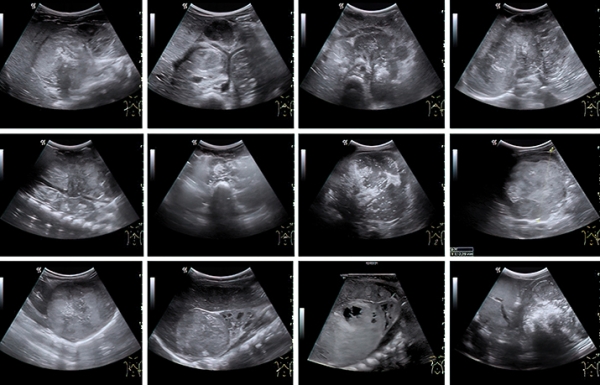

К сожалению, у значительной части пациентов на момент постановки диагноза болезнь уже в распространенной форме. Чаще всего опухоль распространяется в лимфатические узлы, печень, кости и костный мозг (см. рис. 1).

Хотя окончательный диагноз нейробластомы выносится на основе биопсии, взятой во время операции, впервые эту опухоль обнаруживает врач УЗД при скрининговом исследовании плода, на профилактическом осмотре или при обследовании ребенка, которого привели с конкретными жалобами.

Во время УЗИ на амбулаторном этапе забрюшинная опухоль, как правило, определяется по достижении так называемого диагностического объема в несколько кубических сантиметров. При этом врач уверенно может установить факт наличия образования, его эхоструктуру, чего уже достаточно для направления ребенка на дообследование (см. рис 2).

Рисунок 2. Сонографические варианты нейробластомы.

Наибольшие трудности специалист УЗД испытывает при установлении органной принадлежности опухоли, когда она уже достигла больших размеров. К примеру, медиана диагностического объема впервые установленной нейробластомы у младенца составляет 75 (26–208) см3, а для опухоли почки и того больше — 317 (226–524) см3. Именно эти новообразования приходится дифференцировать, в том числе и в онкологическом центре, т. к. химиотерапевтическое лечение опухоли Вильмса в ряде случаев начинают по результатам диагностики на основе визуализирующих методов исследования.